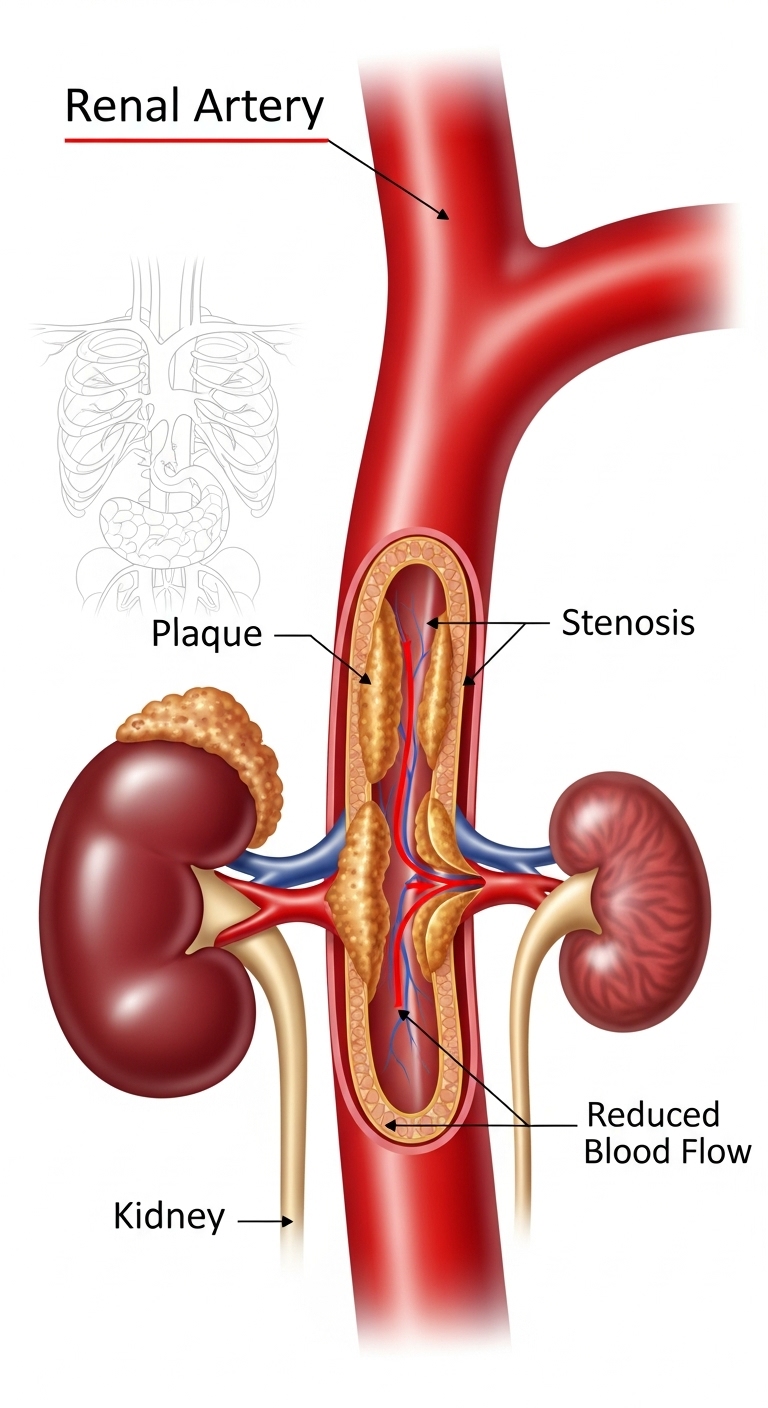

Renal artery stenosis (RAS) is a condition where the arteries that supply blood to your kidneys become narrowed or blocked. This kidney artery narrowing reduces blood flow to the kidneys, leading to high blood pressure and potentially serious complications if left untreated. Understanding this condition is the first step toward effective management and recovery.

Several factors can contribute to the development of renal artery stenosis:

Without proper treatment, renal artery stenosis can lead to serious complications: